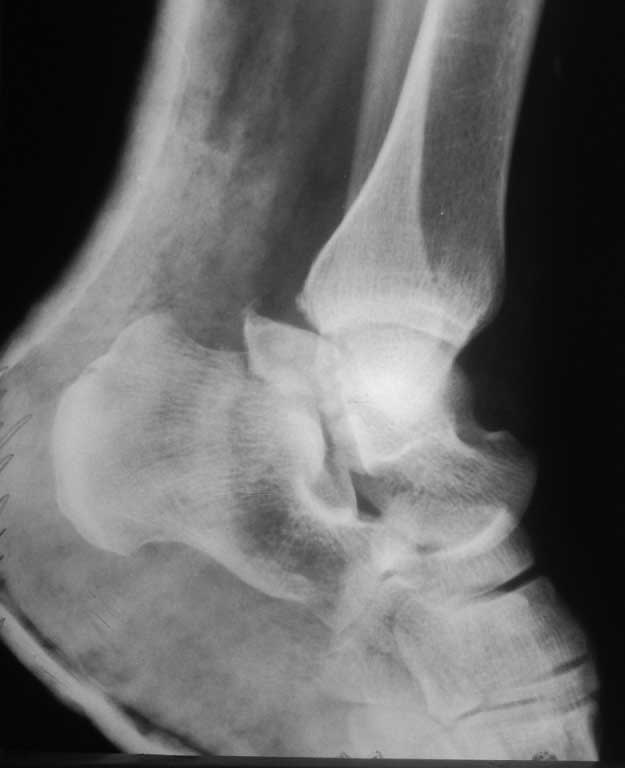

Пациентка 43 года. Через 4 дня поле травмы диагностирован перелом шейки таранной кости с вывихом в таранно- пряточном, таранно- ладьевидном суставах. Попытка закрутой репозиции результата не дала. Наложено скелетное вытяжение. Сейчас попытаюсь добавить снимки(с первого раза не получилось). Первый случай в моей практике, требуется помощь опытных коллег

Попытка закрытой репозиции результата не дала. Наложено скелетное вытяжение. Сейчас попытаюсь добавить снимки(с первого раза не получилось). Первый случай в моей практике, требуется помощь опытных коллег

Хотелось бы увидеть прямую проекцию .

Если есть вывих , то делайте открытое вправление под общим наркозом . Отломки синтезируйте спицами под контролем ЭОПа и накладывайте гипс в положении 90 градусов в голеностопе.